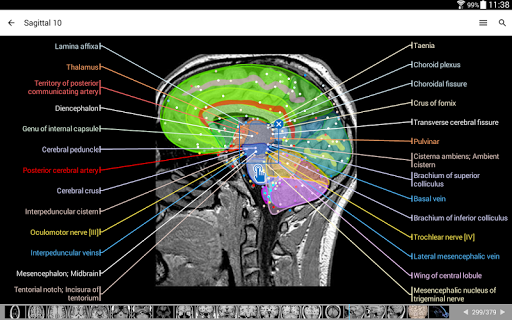

IMAIOS e-Anatomy adalah atlas anatomi manusia untuk dokter, ahli radiologi, mahasiswa kedokteran, dan teknisi radiologi. Dapatkan cuplikan lebih dari 26.000 gambar medis dan anatomi secara gratis sebelum berlangganan atlas anatomi manusia terperinci kami.

e-Anatomy didasarkan pada atlas daring IMAIOS e-Anatomy yang telah memenangkan penghargaan. Bawalah referensi anatomi manusia terlengkap, ke mana pun Anda pergi, di perangkat seluler atau tablet Anda.

e-Anatomy memiliki lebih dari 26.000 gambar yang berisi serangkaian gambar dalam tampilan aksial, koronal, dan sagital serta radiografi, angiografi, gambar diseksi, bagan anatomi, dan ilustrasi. Semua gambar medis diberi label dengan cermat, lebih dari 967.000 label tersedia dalam 12 bahasa termasuk Terminologia Anatomica Latin.

- Gulir set gambar dengan menyeret jari Anda

- Perbesar dan perkecil

- Ketuk label untuk menampilkan struktur anatomi

- Pilih label anatomi berdasarkan kategori